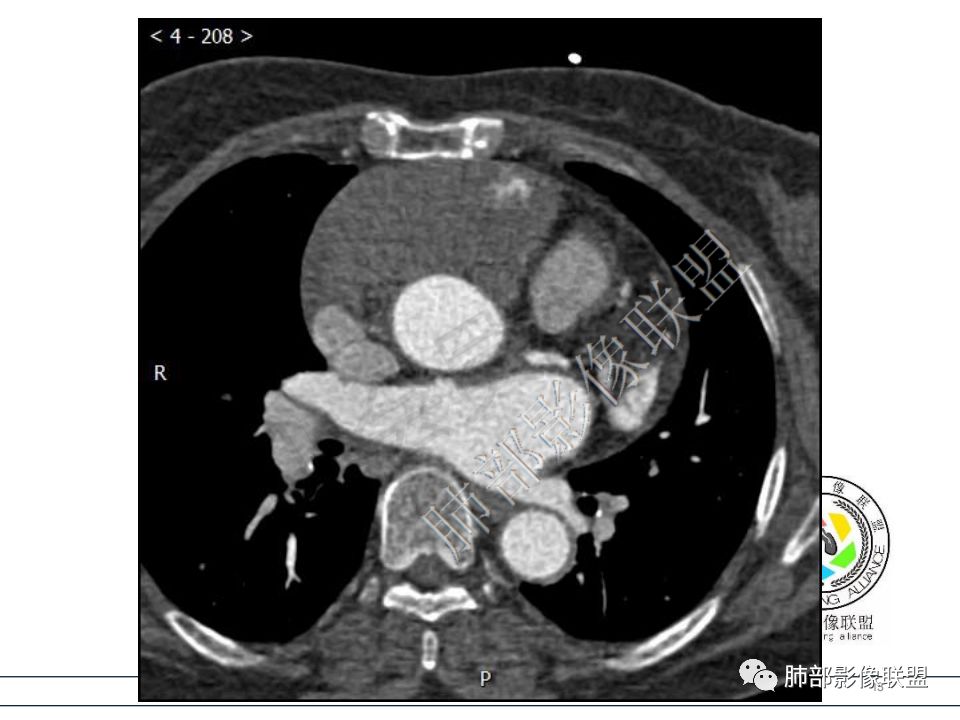

病例一考虑心包来源,病灶从大动脉根部一直延续到心底,明显不均匀强化,没有心包积液,良性?边缘强化,良性先考虑血管瘤。

定位心包,局部与右心房分界不清,右心房受压,冠脉受压,渐进性强化,没有心包积液,考虑心包来源或右心房游离壁来源血管瘤。 医学百科网 | YxBaike.Com

靠近心底层面,与心包延续。

从心底沿右侧房室沟一直延伸至近膈面,心包来源可以解释的通;另外病变与右心室右心房之间的脂肪间隙一直存在。

心包海绵状血管瘤的CT特征为平扫呈边界清楚的圆形或者类圆形低密度肿块,对比增强扫描是诊断海绵状血管瘤的关键。动脉期肿瘤边缘可出现散在斑片状、结节状明显强化灶,接近同层强化大血管密度。静脉期散在的强化灶相互融合同时向肿瘤中央扩展。 医学百科网 | YxBaike.Com

渐进性强化,边界清晰,周围脂肪间隙存在,没有心包积液。 医学百科网 | YxBaike.Com

边界清晰,周围脂肪间隙存在,临近器官受压无受累。 医学百科网 | YxBaike.Com

是不是绝大多数良性肿瘤长在心包里都是塑形生长啊 我看标本 心包太坚韧了。 医学百科网 | YxBaike.Com

对的,心包太硬,很难突破。这例压迫右房、三尖瓣环。 医学百科网 | YxBaike.Com